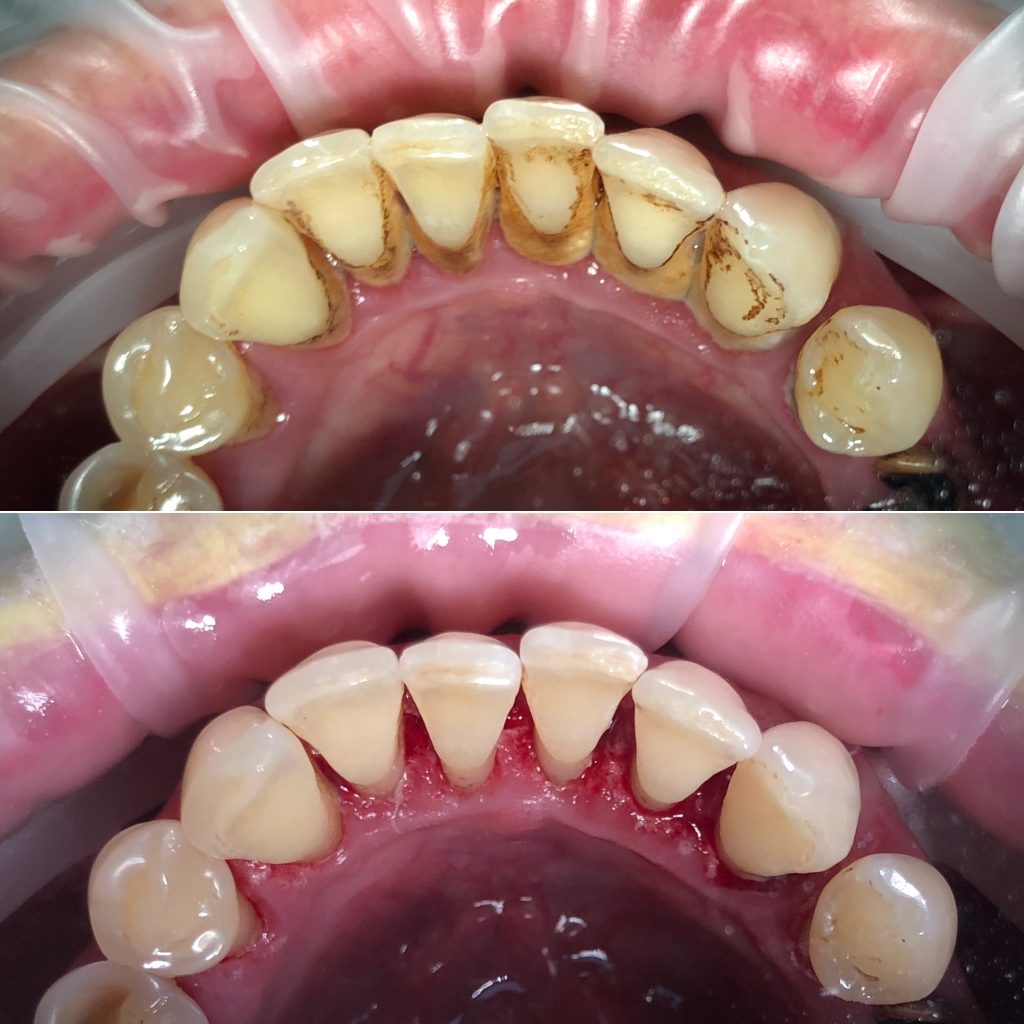

• Профессиональная гигиена полости рта и подбор индивидуальных средств гигиены, профилактика стоматологических заболеваний

• Художественная реставрация фронтального и бокового участка зубов